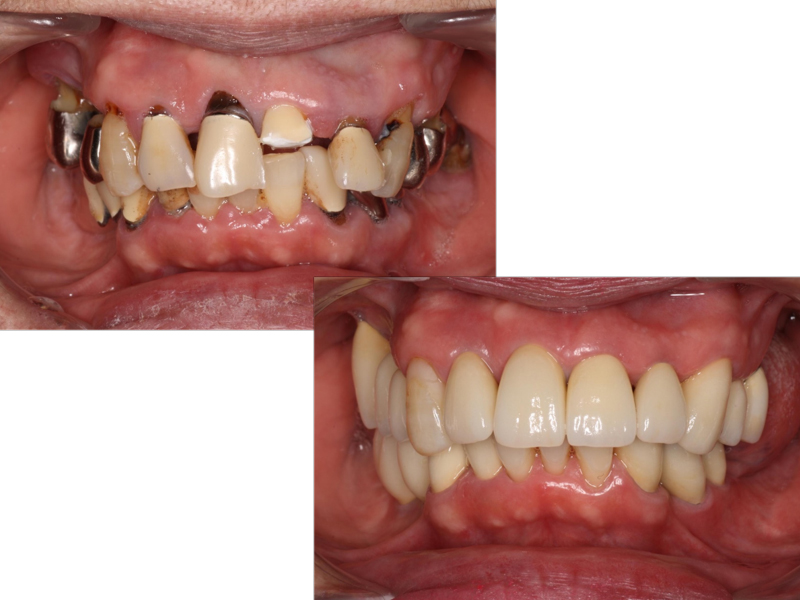

重度歯周病患者様の治療前、治療後ビフォー

重度歯周病患者様の治療前、治療後アフター

初診時口腔内写真

治療終了時口腔内写真